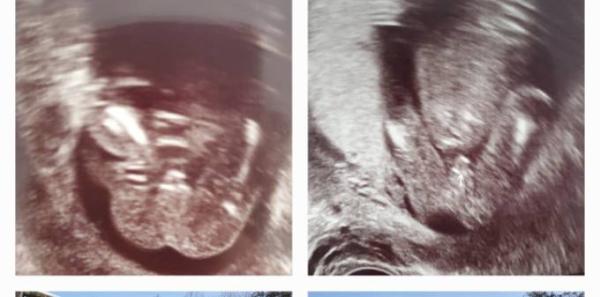

Hallo, im August Forum wurde mir schon geantwortet, aber vielleicht finde ich hier noch ein paar erfahrene Jungen Muttis. Für mich sieht das nach einem Jungen outing aus, nun überlege ich aber ob es vielleicht doch die Nabelschnur sein könnte. Wie sind eure Erfahrungen?? Lieben Gruß Vova

Bild zu Outing- an die Jungs Mamas - Schwanger - wer noch? Rund um die Schwangerschaft

Habe drei Jungs und aktuell noch drei Mädels, bald vier. So sahen nur meine Jungs aus

Das find ich sehr eindeutig. Herzlichen Glückwunsch!!

Sieht für mich auch nach einem Jungen aus und nicht nach Nabelschnur. Bei meinem kleinen Mann sieht es auch so aus .

Hubdertpro ein Junge. Herzlichen Glückwunsch

Natürlich sehe ich da etwas. Nicht selten ist es aber dann doch die Nabelschnur gewesen. Deswegen frage ich nach Erfahrungen.